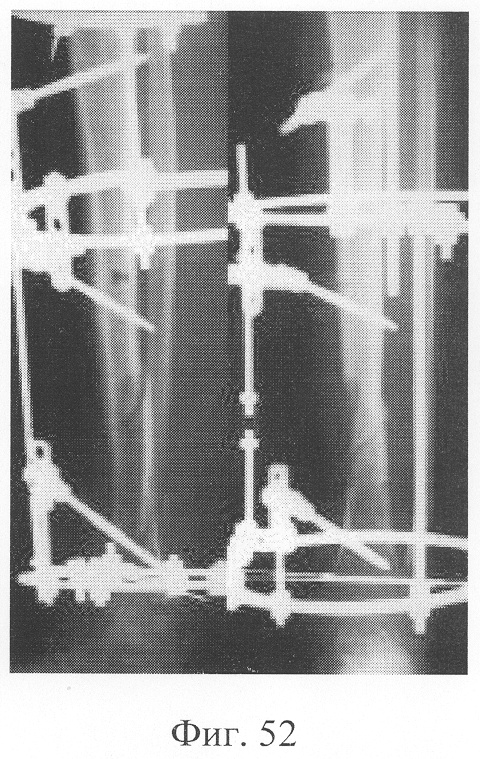

Больной П., 46 лет, поступил для планового оперативного лечения с диагнозом «ложный сустав левой большеберцовой кости» (фиг.47-49 – клинические и рентгенологические данные до операции). В анамнезе открытый перелом обеих костей голени, по поводу которого после проведения первичной хирургической обработки раны был наложен аппарат внешней фиксации с одномоментной репозицией. В связи с замедленной консолидацией проводилась микрокомпрессия и микродистракция, что не имело четкого положительного эффекта. Через 11 месяцев после травмы отмечалась выраженная патологическая подвижность при клинической пробе, рентгенологически отмечены признаки формирования ложного сустава. Аппарат внешней фиксации был демонтирован, и после заживления ран выполнена операция: экономная резекция костных фрагментов, фиксация в аппарате, костная пластика деминерализованным костным трансплантатом, заселенным аутологичными мезенхимальными стволовыми клетками по предложенной методике. В послеоперационном периоде дренажи удалены на 2-е сутки, швы сняты на 14 сутки, с 5-х суток разрешена ходьба при помощи костылей, с 7-х суток нагрузка на оперированную конечность (фиг.50-52 – клинические и рентгенологические данные в процессе лечения). Аппарат внешней фиксации демонтирован через 3 месяца при клинико-рентгенологической картине сращения (фиг.53-55 – результат лечения).